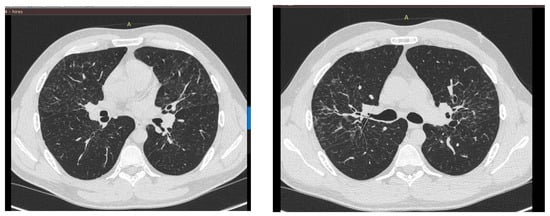

4. Different Manifestations and Causes of Pulmonary and Intrathoracic Lymph Node Sarcoidosis